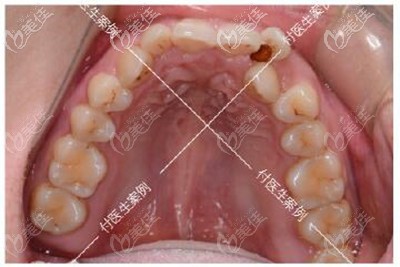

術(shù)前照片:

牙齒診斷:牙齒擁擠不齊+深覆合+單顆反頜+下頜方形牙弓

牙齒矯正方案:拔牙2顆、佩戴3m金屬自鎖托槽